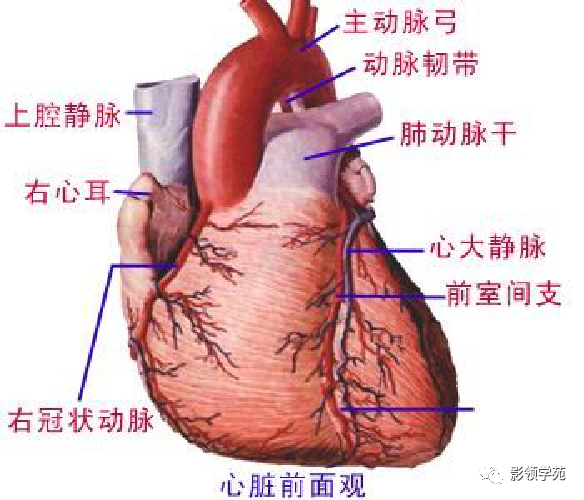

心血管系统

心血管系统